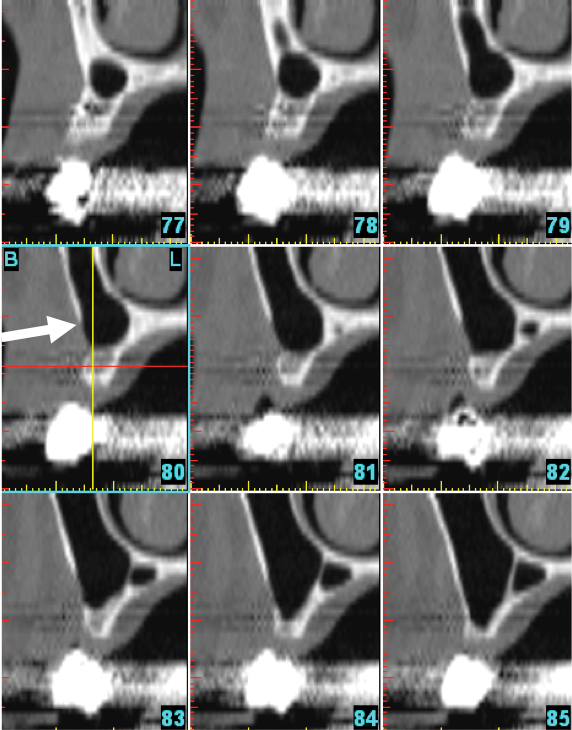

Fig 6. No anterior loop of the mental foramen: nine consecutive cross-sectional views. Sections anterior to the mental foramen do not demonstrate any radiolucency that corresponds to the loop of the inferior alveolar nerve. Arrow is pointing to the bone anterior to the mental foramen, which does not demonstrate a loop.

Figure 6